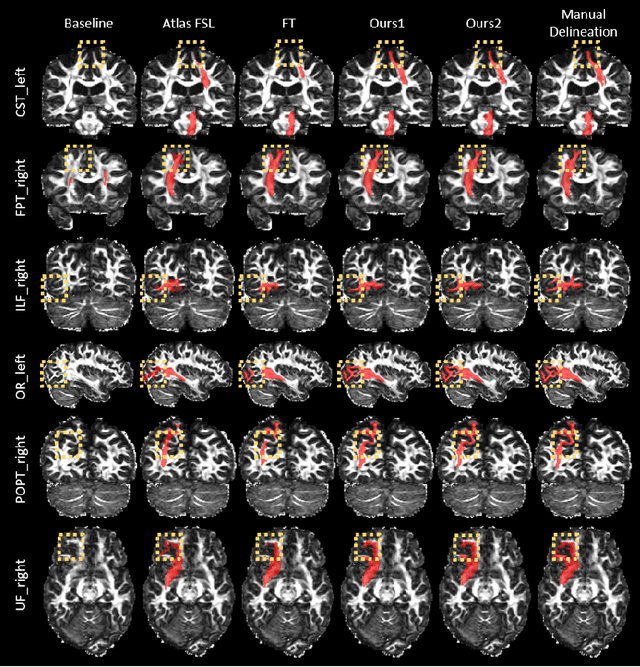

Convolutional neural networks (CNNs) have achieved stateof-the-art performance for white matter (WM) tract segmentation based on diffusion magnetic resonance imaging (dMRI). These CNNs require a large number of manual delineations of the WM tracts of interest for training, which are generally labor-intensive and costly. The expensive manual delineation can be a particular disadvantage when novel WM tracts, i.e., tracts that have not been included in existing manual delineations, are to be analyzed. To accurately segment novel WM tracts, it is desirable to transfer the knowledge learned about existing WM tracts, so that even with only a few delineations of the novel WM tracts, CNNs can learn adequately for the segmentation. In this paper, we explore the transfer of such knowledge to the segmentation of novel WM tracts in the few-shot setting. Although a classic fine-tuning strategy can be used for the purpose, the information in the last task-specific layer for segmenting existing WM tracts is completely discarded. We hypothesize that the weights of this last layer can bear valuable information for segmenting the novel WM tracts and thus completely discarding the information is not optimal. In particular, we assume that the novel WM tracts can correlate with existing WM tracts and the segmentation of novel WM tracts can be predicted with the logits of existing WM tracts. In this way, better initialization of the last layer than random initialization can be achieved for fine-tuning. Further, we show that a more adaptive use of the knowledge in the last layer for segmenting existing WM tracts can be conveniently achieved by simply inserting a warmup stage before classic fine-tuning. The proposed method was evaluated on a publicly available dMRI dataset, where we demonstrate the benefit of our method for few-shot segmentation of novel WM tracts.